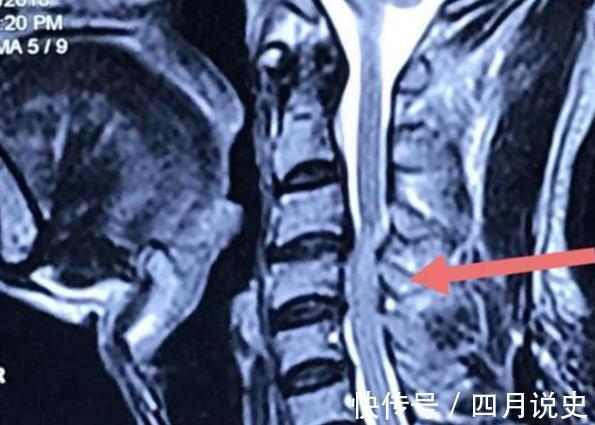

医生对晓峰做了基本的查体检查,又给晓峰开了MRI的检查,医生拿着检查单子告诉晓峰,具体情况,

医生:你的MRI结果提示你椎间盘向后突出,脊髓明显受压,椎管狭窄,可以基本断定为颈椎脊髓压迫症。

患者血尿常规正常,体重无明显减轻。颈椎MRI显示颈椎3、4间隙脊髓受压明显,椎管狭窄明显。可诊断为脊髓压迫症。

医生在显微镜下对晓峰进行颈椎前路间盘切除植骨融合术,切除了在3、4节脊柱中病变突出的椎间盘,配合神经根减压,将脊柱于椎间植骨进行融合。

晓峰在术后复查了颈椎生理曲度恢复,术后复查MRI也显示晓峰的脊髓压迫显示基本解除。